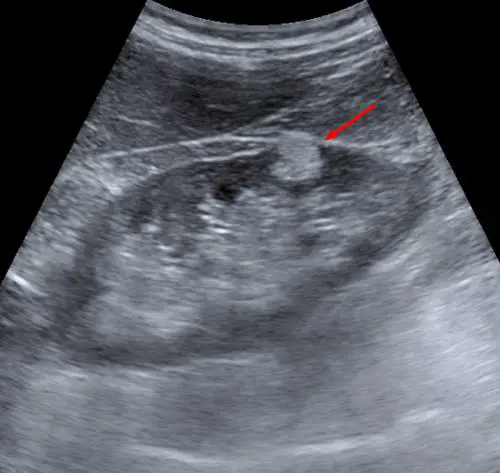

Se le dimensioni della massa tumorale superano i quattro centimetri di diametro, l'unica strategia terapeutica è quella chirurgica

L’ecografo è più attendibile ed è facile e veloce. In un'ora e mezzo si possono fare anche 25-30 esami

Se provocano sintomi o se di grosse dimensioni, queste escrescenze devono essere rimosse chirurgicamente